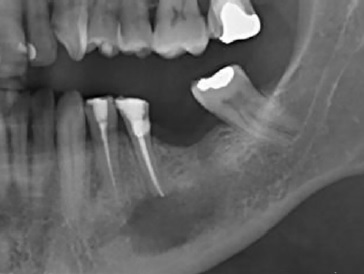

Ao exame radiográfico (Figura 2) foi possível identificar uma área radiolúcida unilocular, de contorno mal definido, na região periapical do dente 35, estendendo-se para o periápice do dente 34 e região edêntula correspondente ao 36. Para melhor visualização da extensão da lesão e sua relação com o canal mandibular foi realizada Tomografia Computadorizada de Feixes Cônicos. Cortes axiais e parassagitais mostraram rutura das corticais ósseas vestibular e lingual do corpo da mandíbula, além do íntimo contato da lesão com o canal mandibular (Figura 3), revelando o elevado risco de parestesia do nervo alveolar inferior e do seu ramo mentoniano, após intervenção cirúrgica.

Figura 2 Radiografia panorâmica inicial mostrando área radiolúcida unilocular, de contorno mal definido, na região periapical do dente 35, medindo aproximadamente de 1x2 cm, se estendendo para o periápice do dente 34 e região edêntula correspondente ao 36.